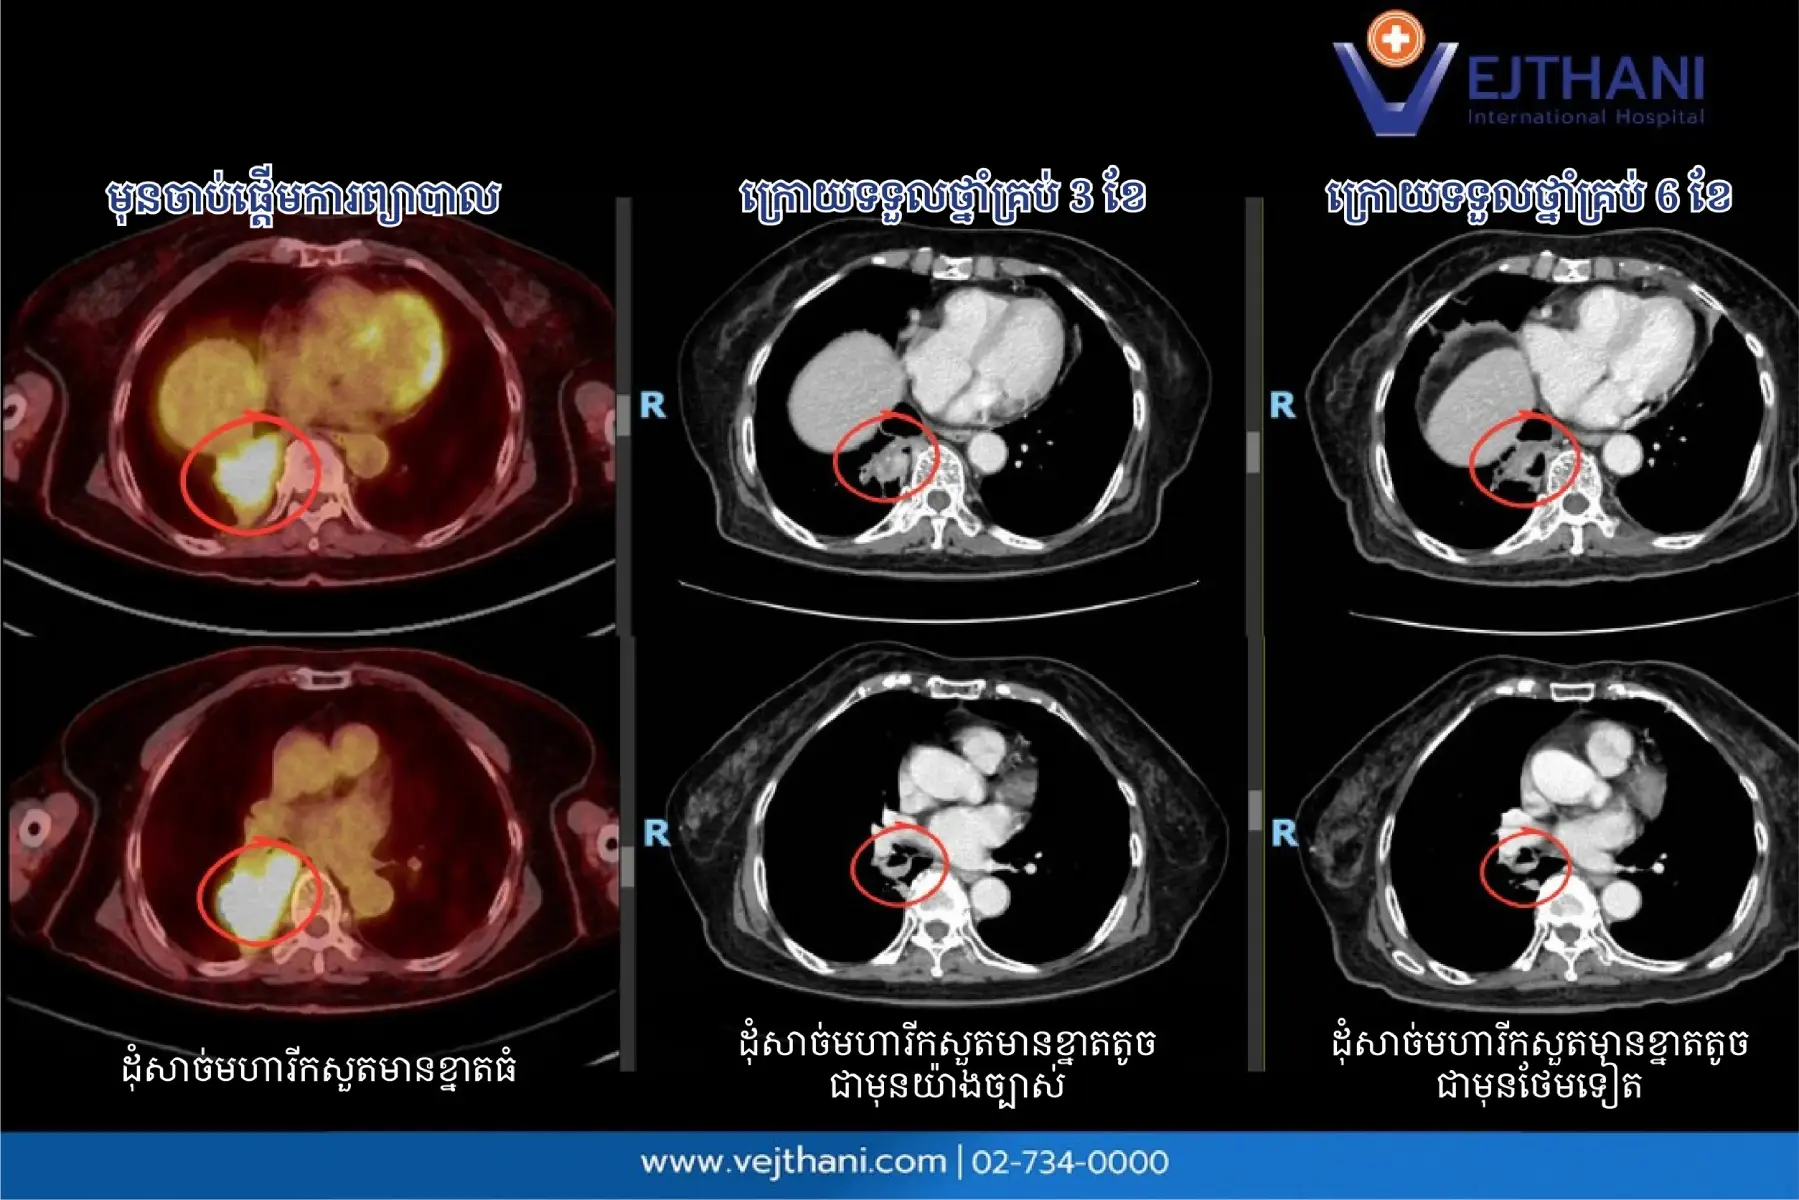

អ្នកជំងឺម្នាក់នេះបានទទួលការធ្វើរោគវិនិច្ឆ័យថាមាន ជំងឺមហារីកសួតប្រភេទ NSCLC ដំណាក់កាលរាតត្បាត និងលទ្ធផលពីការធ្វើកោសល្យវិច័យបានបង្ហាញឱ្យឃើញថា ការបម្លែងខ្លួនប្រភេទ KIF5B-RET fusion វេជ្ជបណ្ឌិតបានរៀបចំផែនការព្យាបាលជាមួយនឹងថ្នាំ Selpercatinib ដែលជាថ្នាំគោលដៅ RET inhibitor ក្នុងទម្រង់ថ្នាំលេបតាមមាត់ ជាការព្យាបាលរូបមន្ដដំបូងចំពោះអ្នកជំងឺម្នាក់នេះ ដោយមិនចាំបាច់ប្រើការព្យាបាលដោយគីមី ដោយលទ្ធផលនៃថតកាំរស្មីតាមដានបង្ហាញឪ្យឃើញថា៖